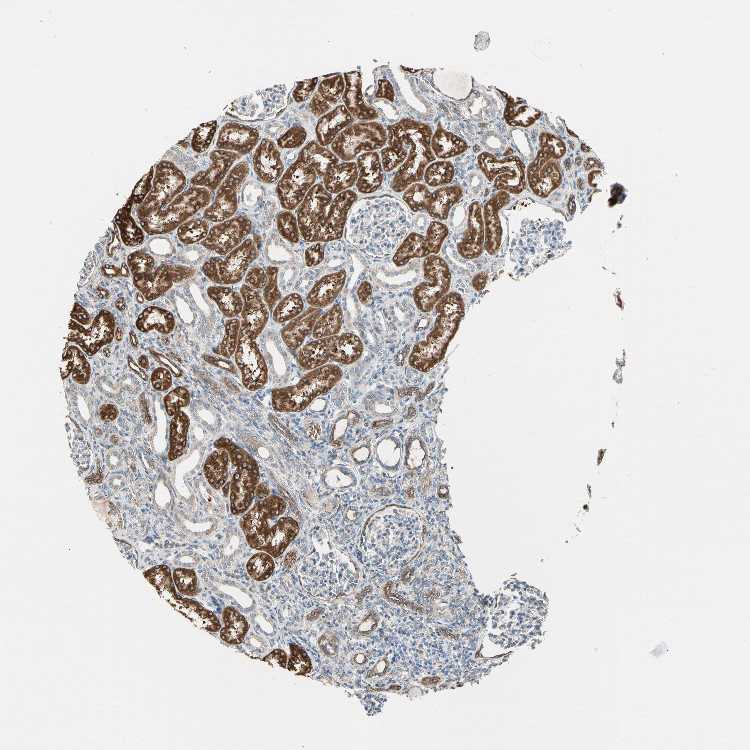

TISSUE PRIMARY DATA KIDNEY Show tissue menu

KIDNEY - Antibody stainingi

Antibody staining in the annotated cell types in the current human tissue is reported as not detected, low, medium, or high, based on conventional immunohistochemistry profiling in selected tissues. This score is based on the combination of the staining intensity and fraction of stained cells.

Each image is clickable and will lead to virtual microscopy that enables deeper exploration of all samples and also displays staining intensity scores, fraction scores and subcellular localization as well as patient and tissue information for each sample.

Antibody HPA008001Antibody CAB025518

Cells in glomeruli Not detectedNot detected

Cells in tubules HighHigh